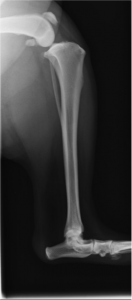

今回は体重28kgの大きな雑種犬でした。触診により膝の典型的な緩みが検出され、伸屈時にclickがあり半月板の損傷も示唆されました。術前のTPAは25度でした。

術前レントゲン